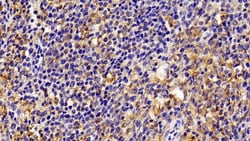

IBA1 Polyclonal Antibody for Western Blot, IHC (P)

Ionized calcium-binding adapter molecule 1 (IBA1), also known by its gene name AIF1, is a protein expressed predominantly by microglia in the brain and spinal cord. This protein belongs to the EF-hand calcium-binding protein family and plays a crucial role in microglial activation and migration in response to brain injury or neuroinflammation. IBA1's function is integral to microglial motility and phagocytic activity, facilitating the cellular response to pathogenic stimuli and promoting tissue homeostasis and repair in the central nervous system. IBA1 serves as a reliable marker for activated microglia in various neurological disorders, including Alzheimer's disease, Parkinson's disease, and multiple sclerosis, where increased expression correlates with disease progression and severity. The protein's structural features enable it to bind calcium ions, inducing conformational changes that activate signaling pathways essential for microglial function. Its expression is highly regulated by inflammatory cytokines, underpinning its role in neuroimmune responses. Due to its specific expression in microglia during pathological conditions, IBA1 is widely used in research as a marker to study microglial status and activity, and it remains a focal point for understanding microglial involvement in neurodegenerative diseases.Specifications

| Immunohistochemistry (Paraffin), Western Blot | |